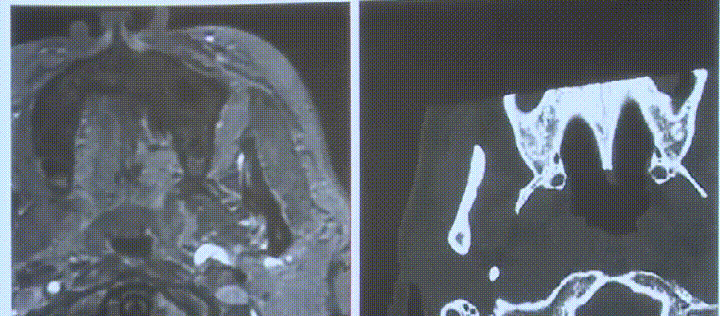

影像显示:巨大肿瘤在生长过程中向颅内延伸,已浸润周围骨质。所幸肿瘤尚未侵犯硬膜内结构,因此必须立即采取干预措施。

最后,福教授植入一张Selastic硅胶片,完成手术。术后MRI复查图像清晰显示解剖结构完整保留,患者无需鼻腔冲洗,几乎无任何并发症发生。“这就是此类手术的魅力所在”福教授总结道。